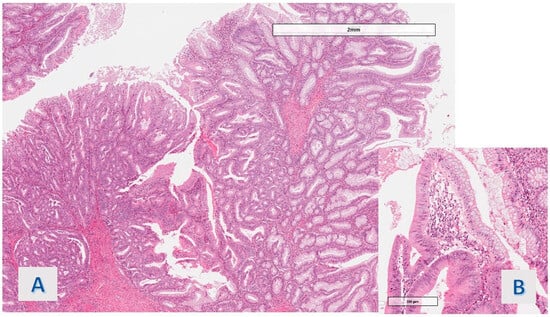

The protruding lesions were coated by an epithelium with hyper mucinous changes (adopting the criteria defined in Section 2) in 11 of the 20 cases (55%) (Figure 1), while the mean rate of the involved samples for a single case was 36.5%. In 9 cases (45%), the hyper mucinous proliferations were associated with hyperplastic/regenerative changes with mild nuclear atypia and mucin depletion. Data about the distribution of IBD subtypes, occurrence of associated conventional (adenomatous) dysplasia, existence of gastric metaplasia (a benign reactive change associated with chronic disease), and grade of activity (in all cases, active disease was detected, except for 1 case in the hyper mucinous group) were matched in the two groups (see Table 2). Associated dysplasia had high-grade features in the case of the group with hyper mucinous changes (Figure 2) and low-grade in the case of the other group (residual low-grade dysplasia after a previous resection for cancerous polyp—pT1 adenocarcinoma).

Figure 1. Case 2: Characteristics of hyper mucinous structures. (A) villous projections (O.M. 200×), (B) cytology of hyper mucinous epithelium, with continuous rows of goblet cells (O.M. 40×).